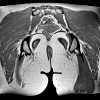

МРТ мягких тканей ягодичной области

МРТ мягких тканей ягодичной области – диагностический метод послойной визуализации тканей с использованием радиоволн и мощного магнитного поля и последующей компьютерной обработкой полученных данных. При необходимости в процессе исследования применяется контрастный препарат. Всего в Казани найдена 1 клиника, где можно сделать МРТ мягких тканей ягодичной области.